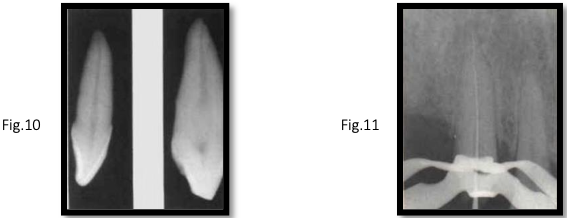

canal anatomy of mx canine

inclination: Labial [fig. 10]

root shape: Straight or slightly distal curve near apex

canal shape:

middle third: broad labio-palatal (forms a bulge)

apical third: round [fig. 11]